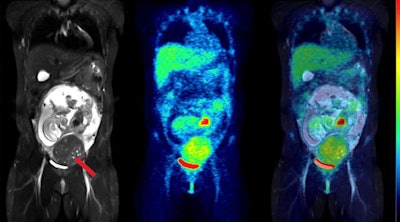

All fetuses were visible in detail on the MRI scans, which allowed the delineation of their body contours. F-18 FDG activity was unevenly distributed in the fetal body. The hearts were generally visible, while the brain showed low uptake, the results showed.

The women were injected with approximately 4 MBq/kg of F-18 FDG (average injected activity, 213 ± 52 MBq) prior to imaging. In part, the fraction of injected activity concentrated by the fetus was derived from manually drawing regions of interest on the MRI slices.

In addition, the highest estimate was observed in early pregnancy (3.2 mGy), while the average of the remaining cases was 1.1 ± 0.5 mGy. The fetus of one woman who had two examinations received a cumulative dose of 3.3 mGy.

This was the first such F-18 FDG dosing study in pregnant women to use imaging entirely acquired with PET/MRI, which allowed detailed visualization of the fetal body contours, they noted. Hence, dose estimations were arguably more accurate than in previous reports, according to the group.